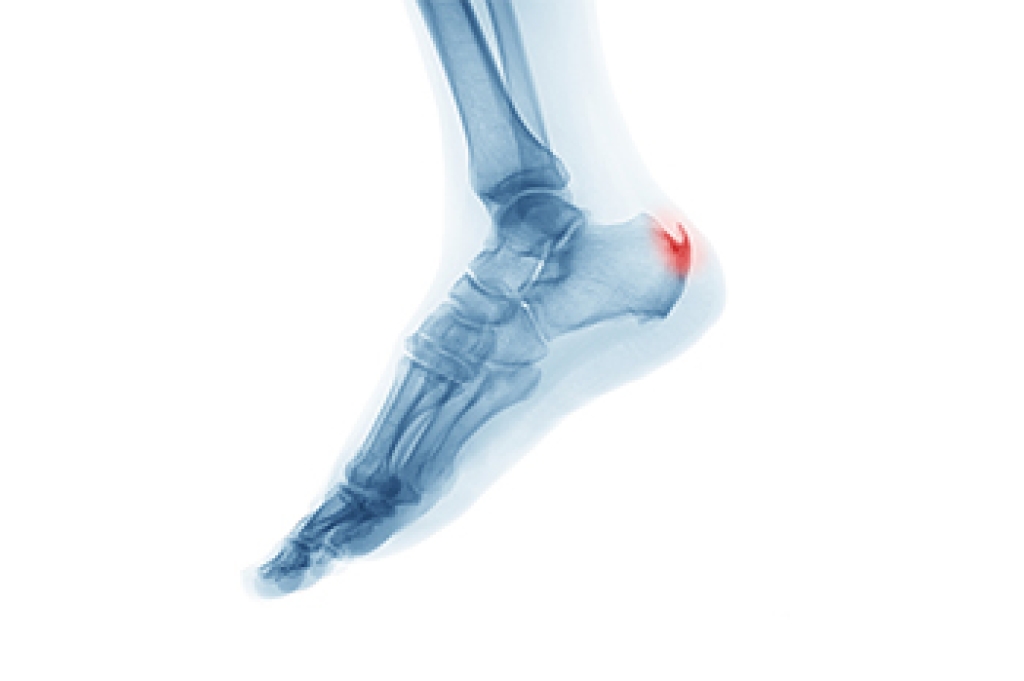

Since heel spurs are often asymptomatic, they are usually only diagnosed when they are found on the heels incidentally during an X-ray taken for another reason. Nevertheless, if you have heel pain, and particularly if you have plantar fasciitis or Achilles tendonitis, it may be worth it to see if you have heel spurs too.